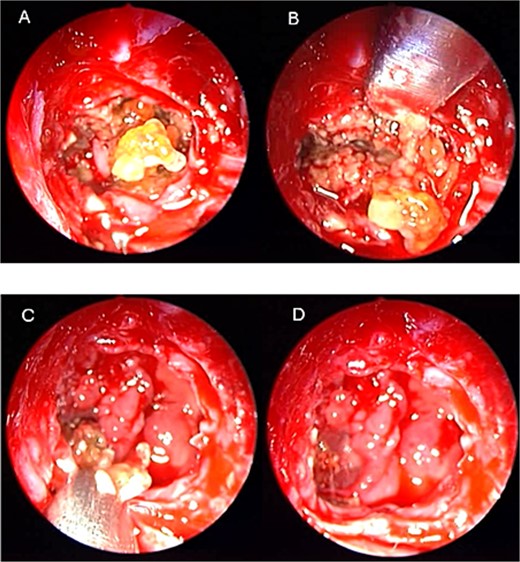

An asthmatic 42-years-old patient who was previously medically treated for allergic rhinitis with no significant improvement. A subsequent CT scan revealed isolated sphenoid sinus disease (Fig. 3). Intra-operative endoscopic findings revealed fungal mud and mucin (Fig. 4A and B) with post-operative (Fig. 4C) endoscopic finding of widely open, clean sphenoid sinus. Further histological examination of the specimen proved the diagnosis of eosinophilic AFS.

Intra-operative (a, b, and c) endoscopic sphenoidotomy showing mud and mucin, with post-operative examination (d) of right optico-carotid recess showing wide and clean sphenoid sinus.